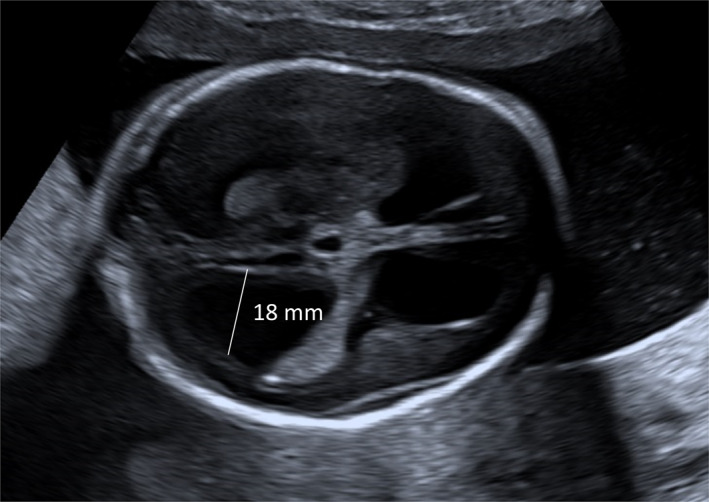

Objective: To investigate the clinical outcome of fetuses with ventriculomegaly (VM), and to identify risk factors for progression of fetal VM in order to improve prenatal counseling. This was a multicenter, retrospective cohort study, comprising 229 cases with VM.

Methods: VM was classified as mild, moderate, or severe and isolated or non-isolated. Genetic data were collected. Differences between VM subgroups were described, and risk factors for progression of fetal VM were identified using logistic regression analysis. Outcome was defined as the percentage of live births, termination of pregnancy (TOP) and intra-uterine fetal demise (IUFD).

Results: Of the 229 cases, 109 (47.6%) had mild VM, 60 (26.2%) moderate VM, and 60 (26.2%) severe VM. Progression of VM occurred in 45/153 cases (29.4%), half of which were in the group with severe VM. Dilatation of the 3rd ventricle and neural tube defects were risk factors for progression of VM. The percentage of live births (excluding cases with TOP and unknown outcome) was 93.1% (54/58) in mild VM, 78.6% (22/28) in moderate VM and 92.6% (25/27) in severe VM. In 12/229 cases (5.2%) IUFD occurred. Genetic analysis was performed in 143/229 (62.4%) of cases, showing (likely) pathogenic abnormalities in 41/143 (28.7%) cases, predominantly in mild, non-isolated VM.

Conclusions: This study confirms the clinical relevance of additional genetic investigations in all types of fetal VMs. Further larger prospective research including clinical follow-up is needed to improve prenatal counseling.